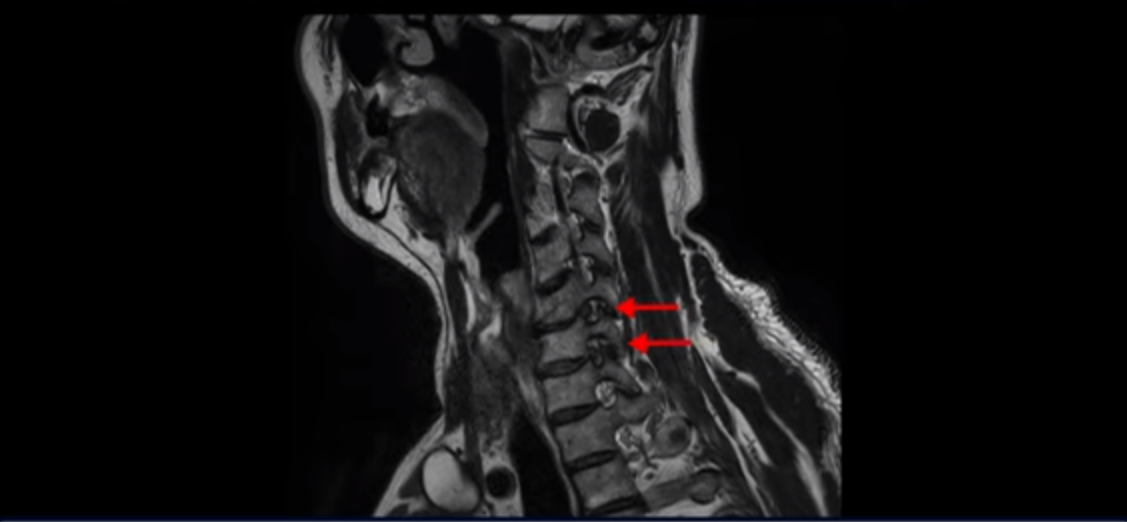

우선 이분 증상은 좌측 어깨와 팔 통증입니다. 이분 MRI를 보면 5번 6번과 6번 7번이 안 좋아 보입니다.

5번 6번에는 오른쪽과 왼쪽 모두 디스크 파열이 있고,

6번 7번에는 왼쪽으로 디스크가 밀려 나와 있습니다.

왼쪽으로 신경이 빠져나가는 추간공을 보면 보시다시피 5번 6번과 6번 7번 신경 구멍이 아래나 위에 비해 막혀있는 게 보입니다.

디스크도 밀려 나와 있고 협착도 있는 겁니다.